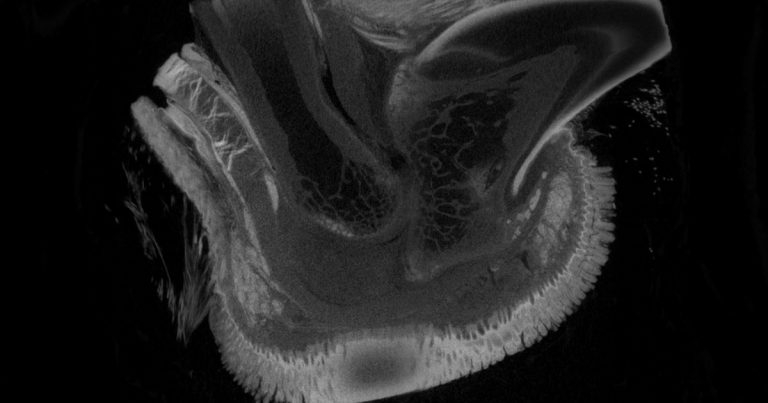

Figure 2. A micro-CT of the digit with a large corn pressing on the deep digital flexor tendon.

A corn is a focal area of pad hyperkeratosis (Figure 1) and can protrude both externally and internally (Figure 2) where it gives the appearance of a hollow root.